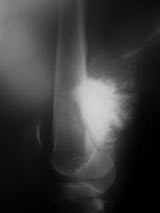

X-Rays:

- Lobulated and ossified exophytic mass (cauliflower-like) adjacent to the cortex; attached to metaphyseal cortex via a broad base

- Centrally, the tumor is radiodense (demonstrates ossification)

- Peripherally there may be small radiolucies that represent low grade cartilaginous lobules, fibrous tissue or fat

- The underlying cortex may be thickened

- There is no periosteal reaction since the tumor comes from the outer layer of the periosteum and therefore does not elevate the periosteum.

- Large tumors encircle the bone

- Appears to have broad attachment to underlying cortex with a cleft between exophytic base and cortex at periphery. This is referred to as a “String Sign” (cleft is often only identifiable on CT scan)